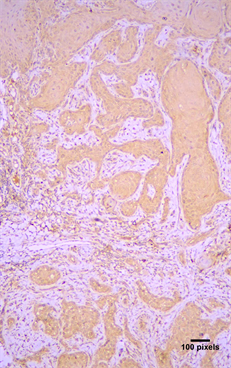

Arp2 and Arp3 expression were cytoplasmic (Figure 1). Arp2 positivity was seen in 79 (89.77%) cases and Arp3 positivity in 78 (88.63%) cases (Table 2). In positive cases, Arp2 expression was graded as (+) in 12.5%, (++) in 28.4% and (+++) in 48.86% of the cases; Arp3 was graded as (+) in 36.36%, (++) in 30.68% and (+++) in 21.59% of the cases (Table 2). Both molecules were co-expressed in 78 cases and there was a statistical significant correlation between in the expression of Arp2 and Arp3 (p < 0.05) (Table 3). Lymphocytes, neutrophils, macrophages, and vascular endothelial cells showed expression of Arp 2/3, as has been previously described in the stroma of malignant tumors [12] [15] [16] [17].

Figure 1. Cytoplasmic immunohistochemical expression of (a) Arp2 (+++) and (b) Arp3 (++) in a moderately differentiated OSCC (streptavidin-biotin-peroxidase immunostaining, original magnification ×10).